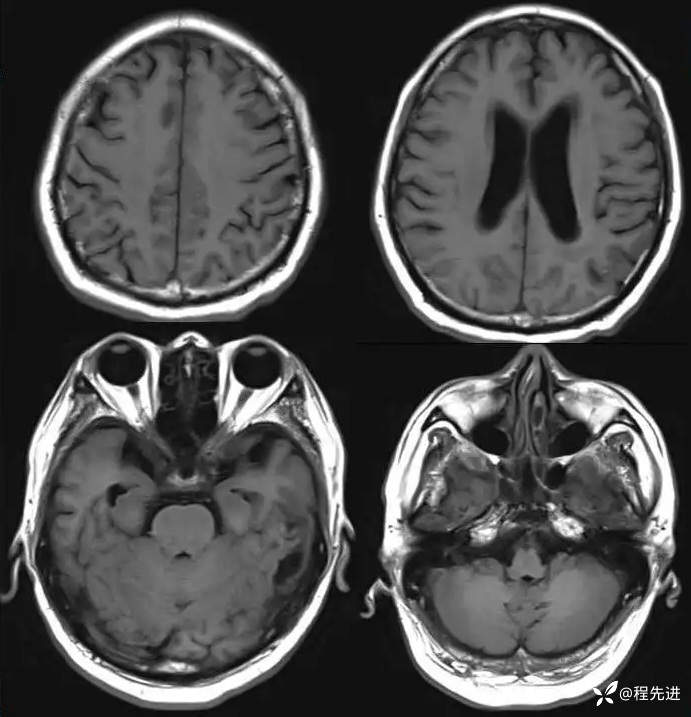

MR平扫+增强: